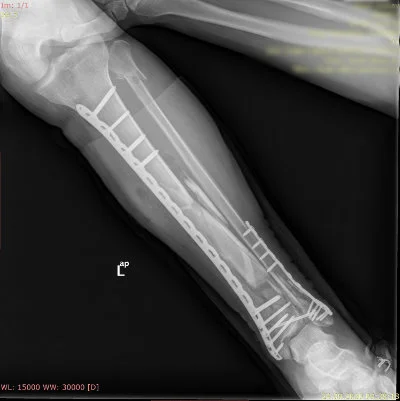

Özellikle kalça, diz, omurga, kol ve bacak kırıkları gibi durumlarda hızlı ve doğru müdahale, iyileşme sürecini büyük ölçüde etkiler.

Prof. Dr. Halil Burç kliniği olarak, bu tür acil durumlarda sadece yaraları dikmek ya da kırığı sabitlemekle yetinmiyor; hastanın uzun vadeli hareket kabiliyetini, konforunu ve yaşam kalitesini korumayı hedefliyoruz. İleri düzey tekniklerle yapılan ameliyatlar sayesinde, hastalarımızın günlük yaşamlarına en kısa sürede ve en az sakatlıkla dönebilmesi için çalışıyoruz.

Görüntüleri büyütmek için resmin üstüne tıklayınız.